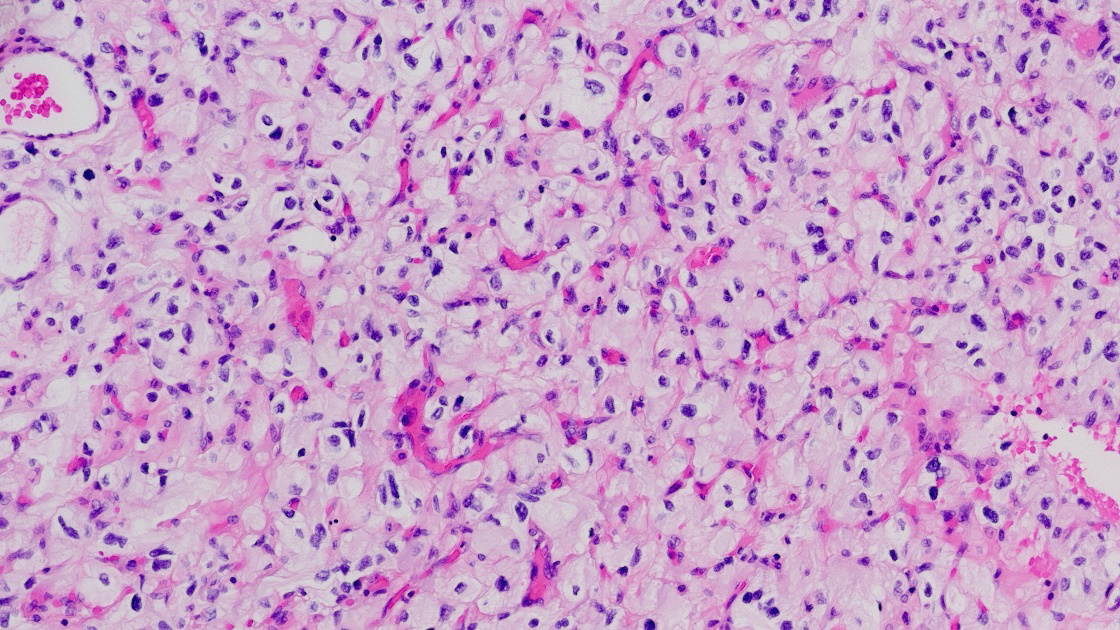

Histologically, hemangioblastomas consist of a collection of neoplastic stromal lipid-laden foamy cells, endothelial cells, and abundant capillaries. The stromal cells are typically lipid-laden and foamy, with clear cytoplasm containing vacuolated lipid droplets [3]. These cells are polygonal to spindle-shaped and often exhibit mild nuclear pleomorphism with degenerative atypia, although mitotic figures are rare [21]. The vascular component consists of thin-walled capillaries interspersed throughout the tumor, forming a reticulated network that is often surrounded by stromal cells and connective tissue [22], (Figure 1).

Hemagioblastona microscopic appearance: neoplastic stromal lipid-laden foamy cells, endothelial cells, and abundant capillaries.

The relative proportions of stromal to vascular elements can vary greatly among tumors, but the overall histologic pattern remains consistent. In classic CNS hemangioblastomas, the stromal cells are arranged between the capillary channels and the tumor borders [3]. The cytoplasm of stromal cells is often eosinophilic, and immunohistochemical staining reveals positivity for markers such as alpha-inhibin, S100, neuron-specific enolase (NSE), and vimentin, supporting their mesenchymal origin [23]. In extra-neuraxial hemangioblastomas, such as those occurring in the kidney or soft tissues, the microscopic features are similar but may show site-specific immunophenotypic variations. For example, renal hemangioblastomas often express PAX8, which can complicate differentiation from clear cell renal cell carcinoma [3, 23]. Despite their benign histology, hemangioblastomas can occasionally exhibit significant nuclear atypia, mimicking malignancy, especially in unusual locations [24]. However, the absence of high mitotic activity, necrosis, and infiltrative growth helps distinguish them from more aggressive neoplasms [3]. The rich vascularity of hemangioblastomas contributes to their radiologic appearance and clinical behavior. The thin-walled vessels are prone to leakage, leading to cyst formation and peritumoral edema. This vascular architecture also underlies the intense enhancement seen on contrast imaging and the potential for hemorrhagic complications in larger lesions [25].